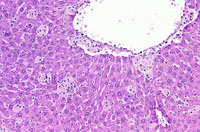

Kupffer cell hyperplasia and hypertrophy is rarely seen in mice. Hypertrophic Kupffer cells may contain pigment in some cases.

Examples of Kupffer cell hyperplasia.